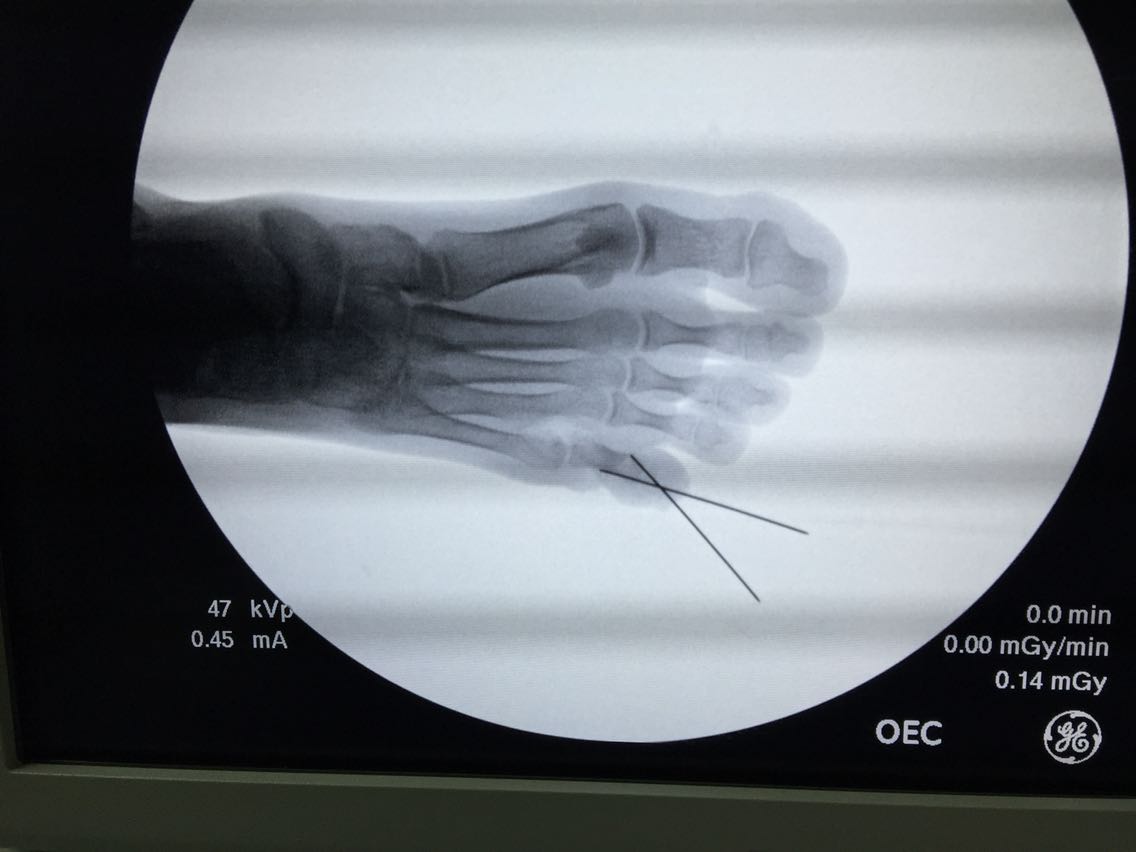

左足先天性多趾并趾畸形矫形手术

左足先天多趾25年 患者出生后发现左足先天多趾畸形,成人后第六趾经常因趾甲挤压致穿鞋走路疼痛不适,今来院要求手术矫形,无其他部位畸形及病史。

诊断:左足先天性多趾畸形 治疗:在麻醉下行多趾畸形矫形手术

手术利用第五趾的甲瓣修复趾甲畸形,去除多余骨骼。